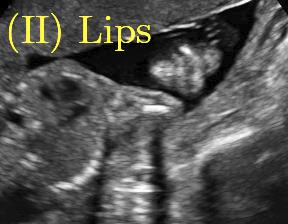

Fig. 6 compares the shadow confidence maps of the state-of-the-art methods and the proposed methods. RW and have the same parameters as used for Table I. The shadow confidence maps of the baseline, the proposed method and the proposedAG method are generated directly from input shadow images by confidence estimation networks. Overall, the proposed method and the proposedAG method achieve more visually reasonable shadow confidence estimation than the baseline and the state-of-the-art on different anatomical structures shown in Fig. 6. The proposed method and the proposedAG method are able to highlight multiple shadow regions while the RW algorithm shows limitations for most cases, especially for disjoint shadow regions.

Row I in Fig. 6 shows a fetal brain image from . The confidence estimation of shadow regions from the baseline, the proposed method and the proposedAG method are similarly accurate since we use fetal brain images to train the confidence estimation networks in these three methods. These outperform [16] and [22]. Rows (II-IV) in Fig. 6 show shadow confidence maps of non-brain anatomy from , including lips, abdominal and cardiac. The baseline failed on unseen data during inference. However, the proposed methods are able to generate accurate shadow confidence maps because of the generalized shadow features obtained by the shadow-seg module. Furthermore, the “Lips” example shows that our method is capable of detecting weaker shadow regions that have not been annotated in manual segmentation. This indicates that the confidence estimation network has learned general properties of shadow regions.